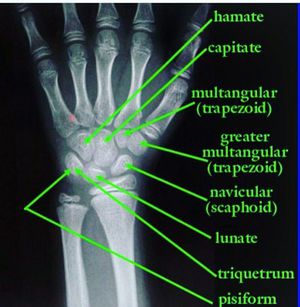

She Looks Too Pretty , Try To Catch Her

mnemonic for students

Anatomy

Bones

Mnemonic

Orthopedics

Mnemonics